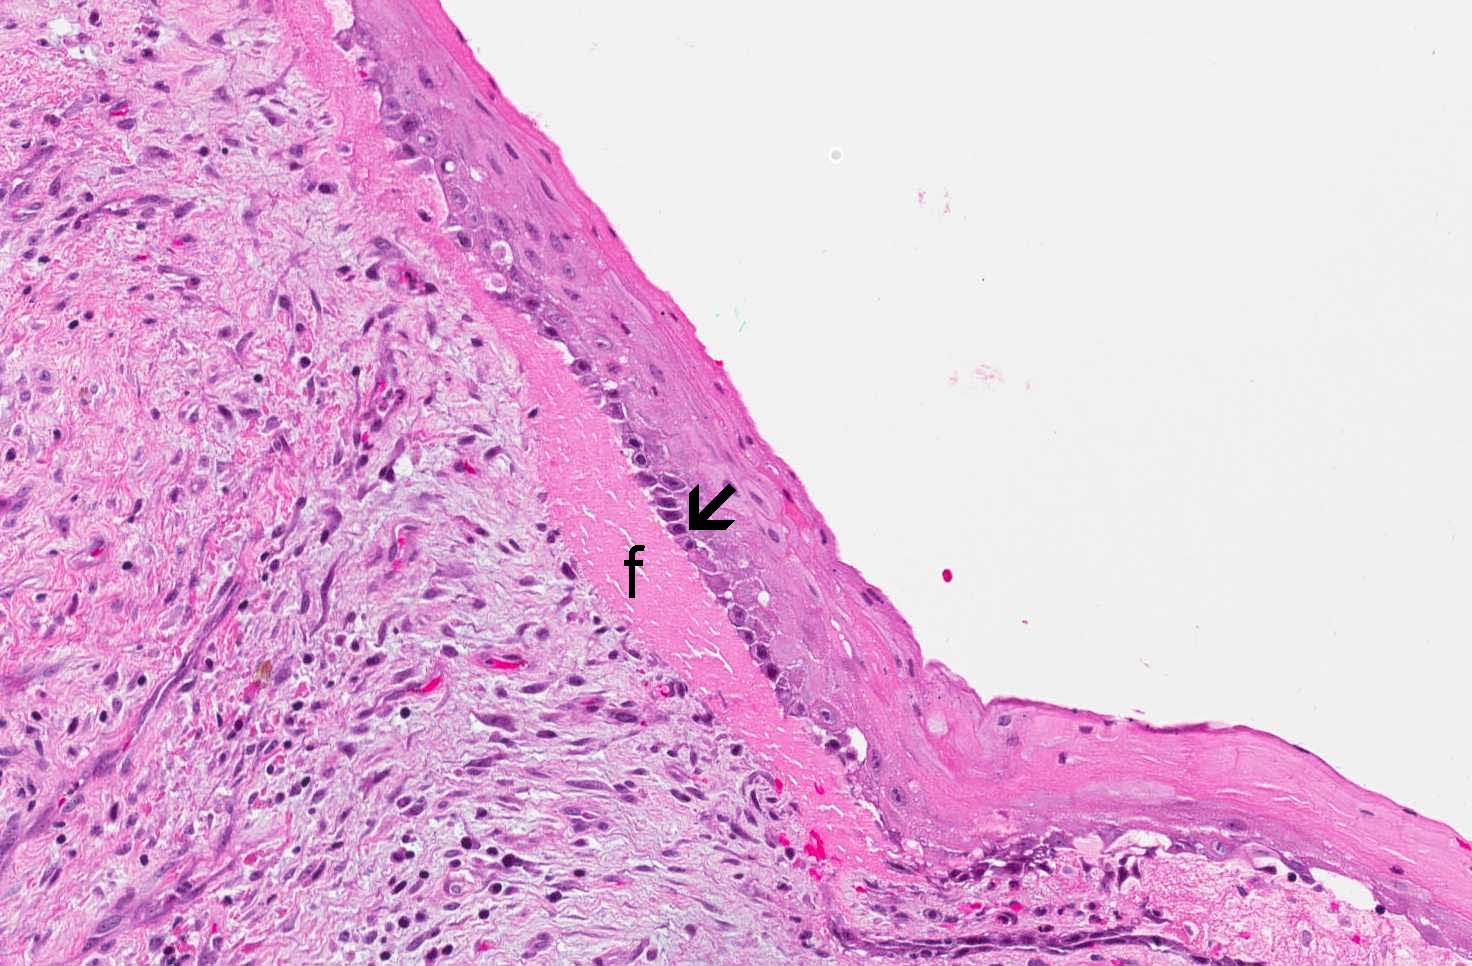

Hematoxylin & eosin

Area 1: Note that there the covering squamous epithelium is thin and free of dysplastic changes. The basal layer is composed of columnar cells with hyperchromatic nuclei, columnar shape, vague palisading arrangement (arrow). A small amount of fibrinous exudate (f) is present in between the squamous epithelium and the underlying stroma. This is not part of the classic features of this type of cyst but rather a result of the inflammation.

• The specimen is composed of stroma composed of fibroconnective tissue lined by a thin squamous epithelium about 5-8 cells thick (area 1). There are some chronic inflammatory cell infiltration in the stroma. Note that parakeratosis (nuclei in surface keratin) is present.

• The basal layer of epithelial cells is composed of hyperchromatic cuboidal to columnar-appearing cells with a tendency for nuclear palisading (area 1 and 2).